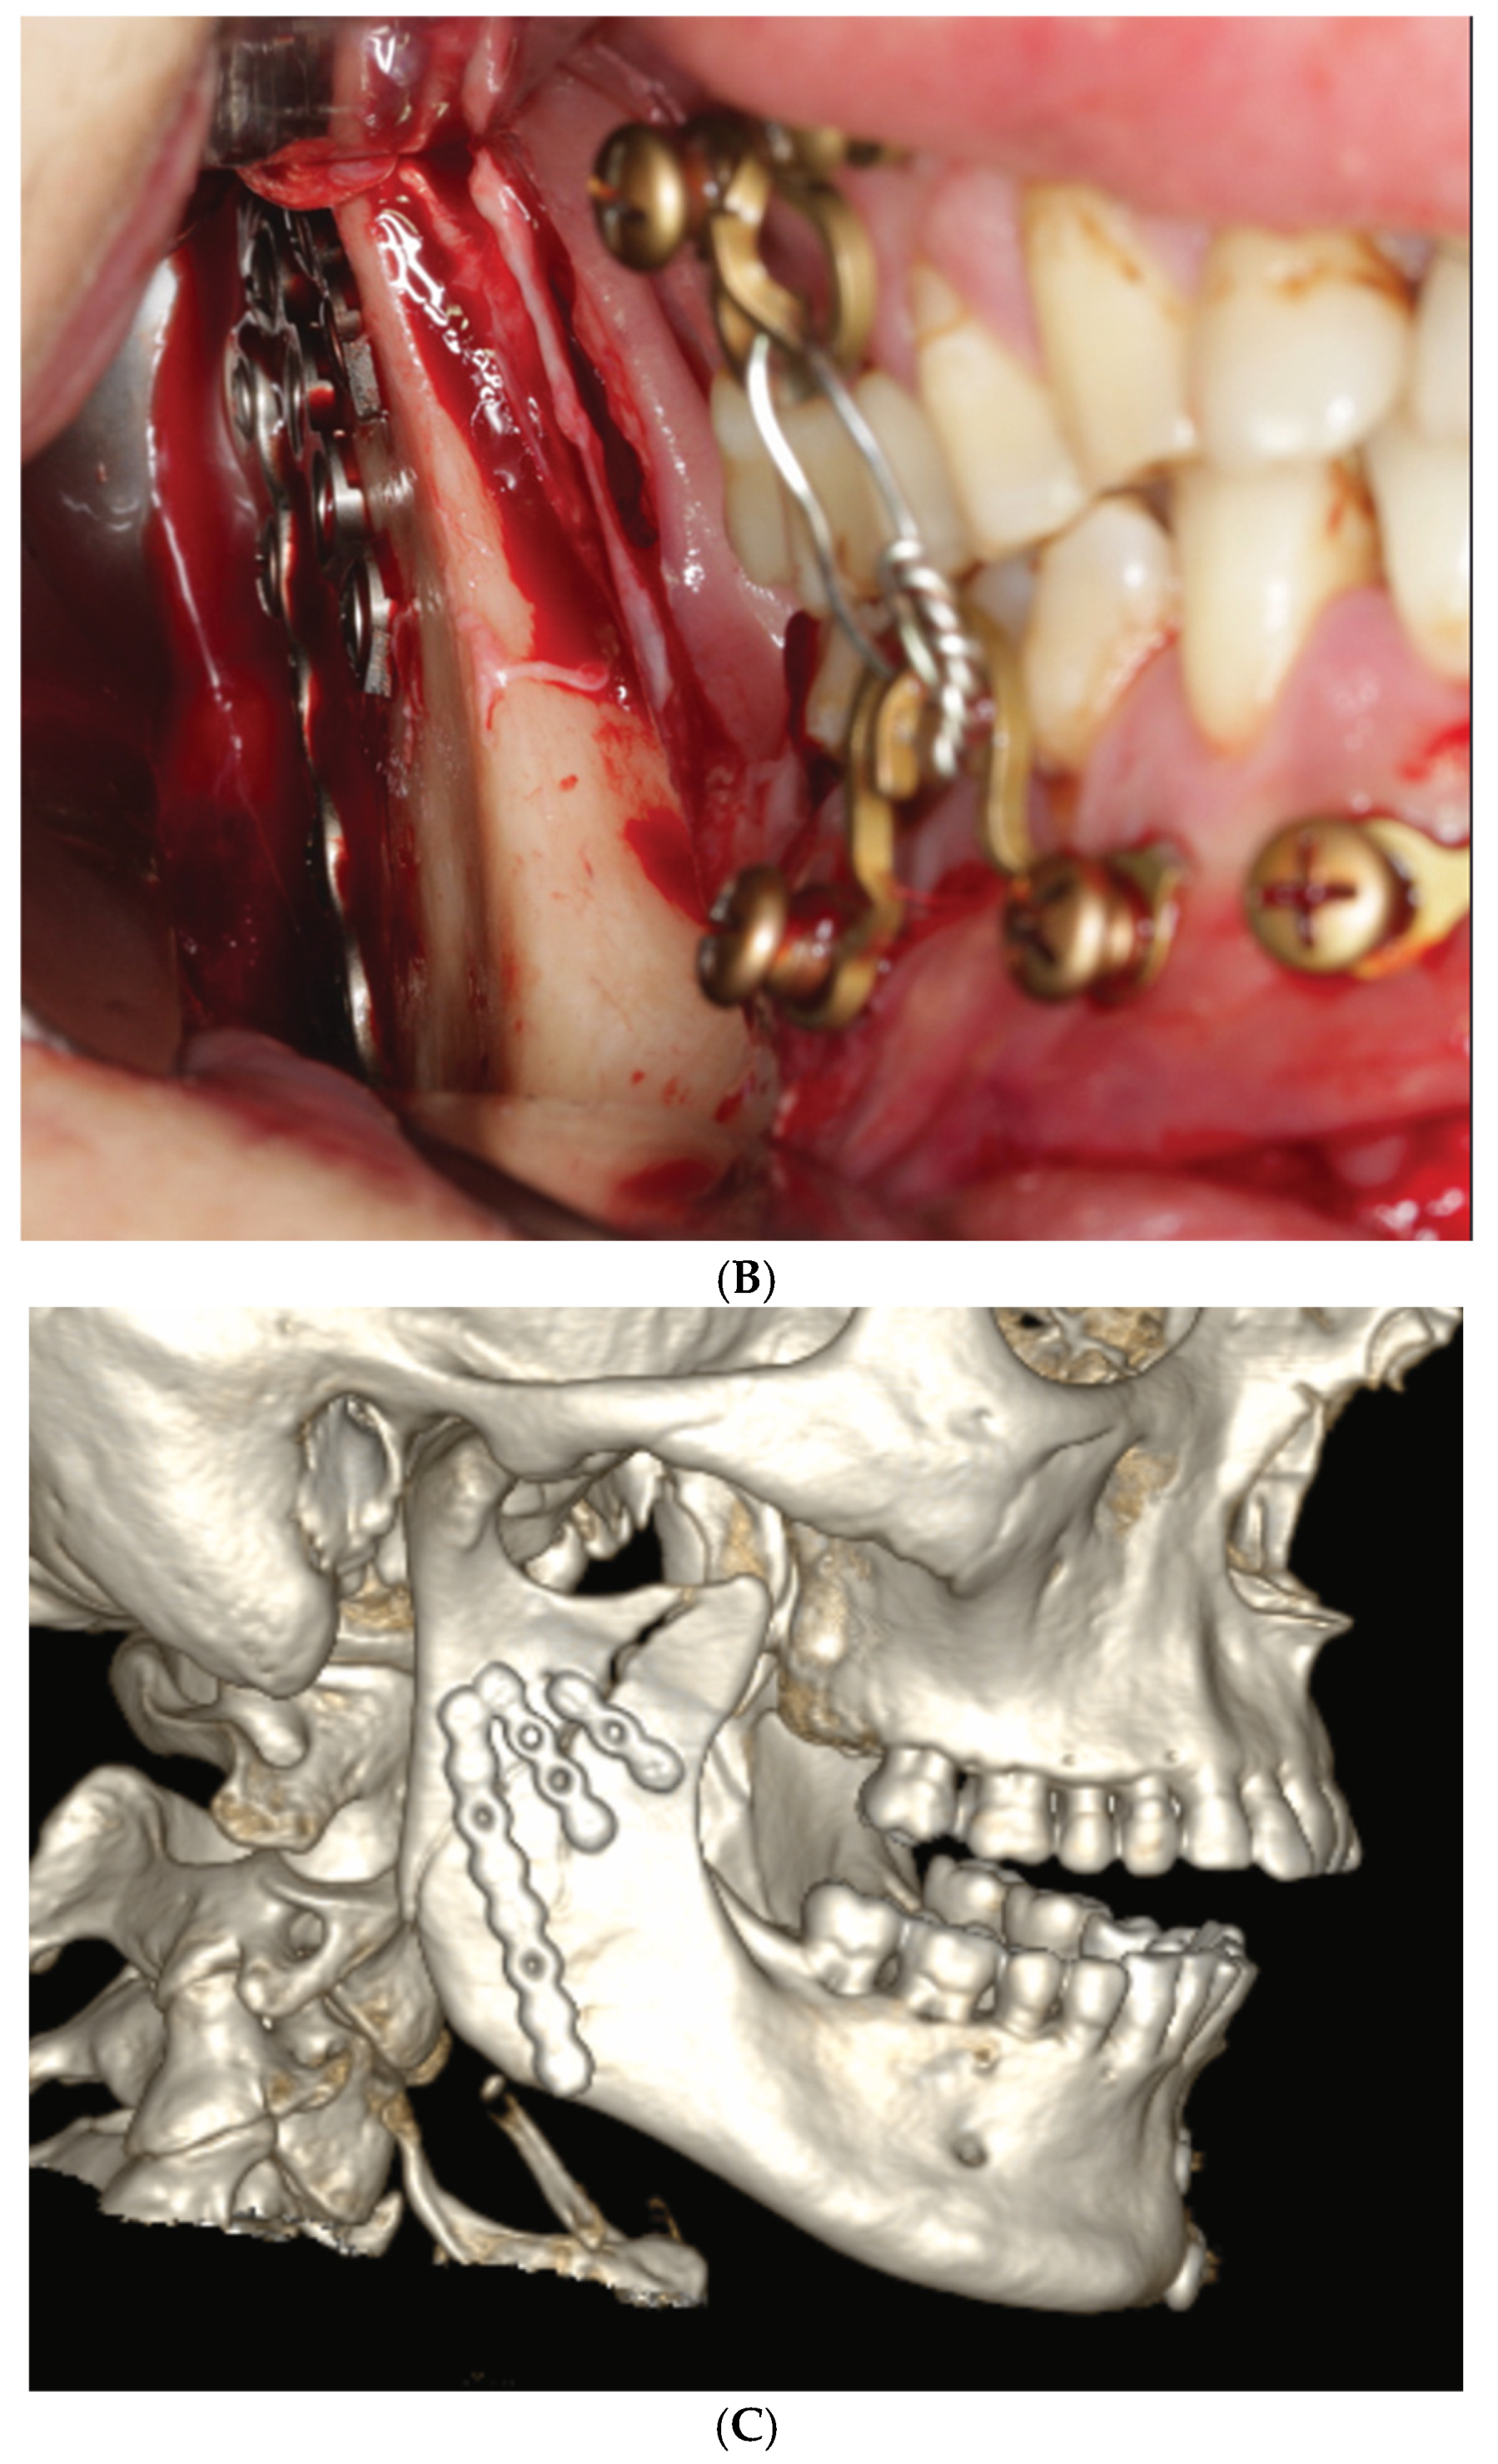

3.3. ‘In-Situ-Bending’ for Fracture Reduction

2.3. Matrix Wave System—Final Design and Technical Description

3.2. Matrix WaveTM Plate MMF System—Mode of Application